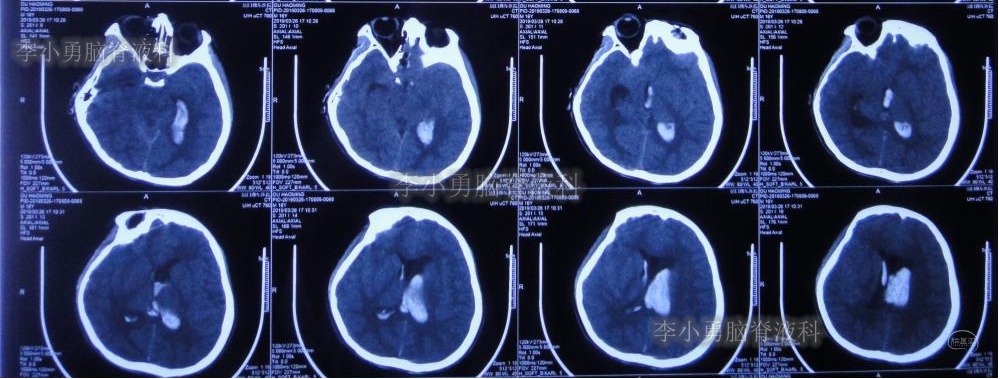

为防止动脉瘤破裂,停止了每日的腰椎穿刺治疗,并积极完善动脉瘤夹闭术前准备。拔除第二次脑室外引流管后12天即2019年4月23日,患者出现哭闹、呕吐、发热及烦躁症状,紧急检查头颅CT(图-8):脑室较前略扩大,未见明显积血。

图-8:2019年4月23日头颅CT:脑室略扩大

为预防动脉瘤再次破裂,于当日下午行脑室内“动脉瘤切除术”+术区脑室外引流术。

但是术后第3天即2019年4月26日,开始出现发热,体温最高38.8℃,且引流管内可见脓血性分泌物,术后给予送检的脑脊液培养示鲍曼不动杆菌。给予抗感染治疗,并继续术区的脑室外引流。

脑室内动脉瘤切除术后2周即2019年5月6日早晨,复查头颅CT(片子遗失)示脑室扩大,积脓。

入院当日行头颅CT(图-10):脑室内“动脉瘤切除术”后改变,术区可见引流管影,脑室扩大。

图-10:2019年5月7日头颅CT:引流术后,脑室扩大